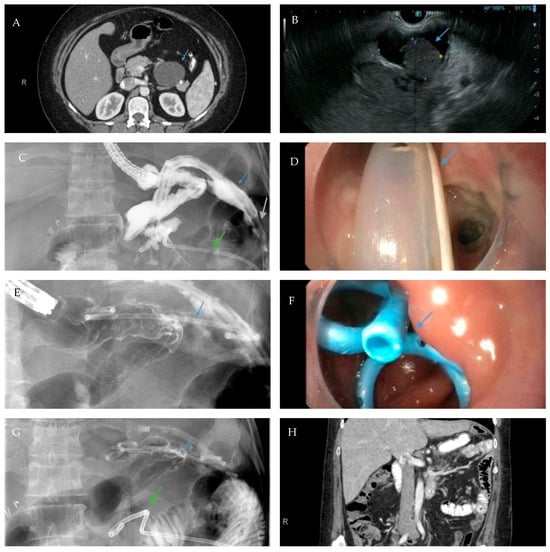

Scheme 5.

Axial view of a computed tomography scan of the abdomen and pelvis with contrast reveals a uniform, thin-walled, cystic lesion of the pancreas, which measures 90 mm × 52 mm × 48 mm, with peripheral calcifications with a BMI of 38 (arrow, A). Endoscopic ultrasound demonstrates an anechoic and hypoechoic lesion of the pancreatic body with two compartments, no septae or internal debris, and an associated mural nodule which was suggestive of a mucinous cystic neoplasm (arrow, B). The patient subsequently underwent a laparoscopic sleeve gastrectomy and a concurrent, open distal pancreatectomy which was complicated by a persistent pancreatic leak as well as a gastric sleeve leak (blue arrow, C) as demonstrated by contrast injected through a percutaneous drain (silver arrow, C). The percutaneous drain is redemonstrated on upper endoscopy (arrow, D). Note the additional percutaneous drain in the pancreatic bed for the postoperative leak (green arrows, C,G). Endoscopic internal drainage using transgastric double-pigtail stents was performed as demonstrated on fluoroscopic imaging (arrows, E,G) and endoscopy (arrow, F). After a prolonged course, the patient had a complete recovery, and a follow-up CT scan of the abdomen and pelvis confirmed the resolution of the leak and the removal of the double-pigtail stents and percutaneous drains (H).

Scheme 7.

Gastric sleeve stenosis in the patient depicted in Scheme 5 was treated with through-the-scope balloon dilation to 20 mm as demonstrated on fluoroscopic image (arrow, left) and upper endoscopy (arrow, middle). Endoscopic contrast injection following dilation revealed improvement in the stenosis and flow of contrast (arrow, right). Note a small residual drain (green arrow, left).